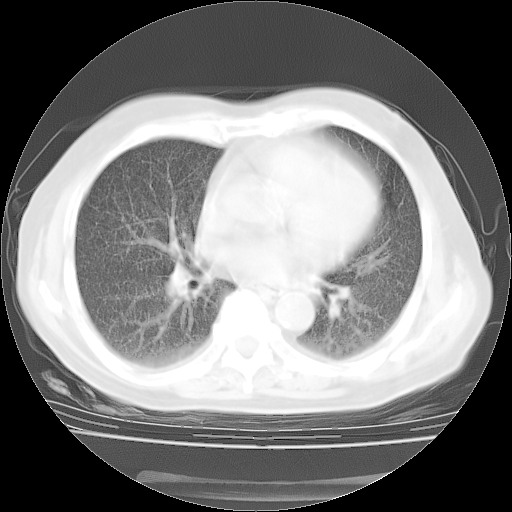

4月28日肺部CT——再次出现类似去年5月9日——透光度降低,(影像科认为)“间质性”改变。

4月28日肺部CT——再次出现类似去年5月9日——透光度降低,“间质性”改变。